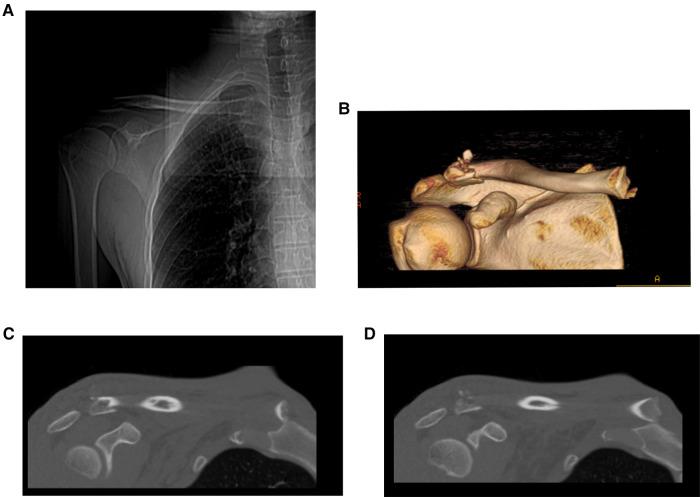

新型胸锁钩钢板在双极锁骨损伤中的应用

Application of a new sternoclavicular hook plate in bipolar clavicle injuries.

To evaluate the safety and effectiveness of using a new sternoclavicular hook plate combined with a shoulder locking hook plate for the treatment of bipolar clavicle injuries.

Retrospective analysis of 7 patients with bipolar clavicle injury, all-male, with a mean age of 51.1 years, who underwent a new sternoclavicular hook plate combined with a shoulder clavicular hook plate implantation.

All 7 patients were fixed with a sternoclavicular hook plate combined with a repositioned shoulder locking hook plate and received 13-24 months of follow-up. There were no postoperative complications, no wound infections, and no plate or screw fractures. The mean ASES score was 94.3 ± 2.8.

The safety and effectiveness of a new sternoclavicular hook plate combined with a shoulder locking hook plate in the treatment of bipolar clavicle injuries.